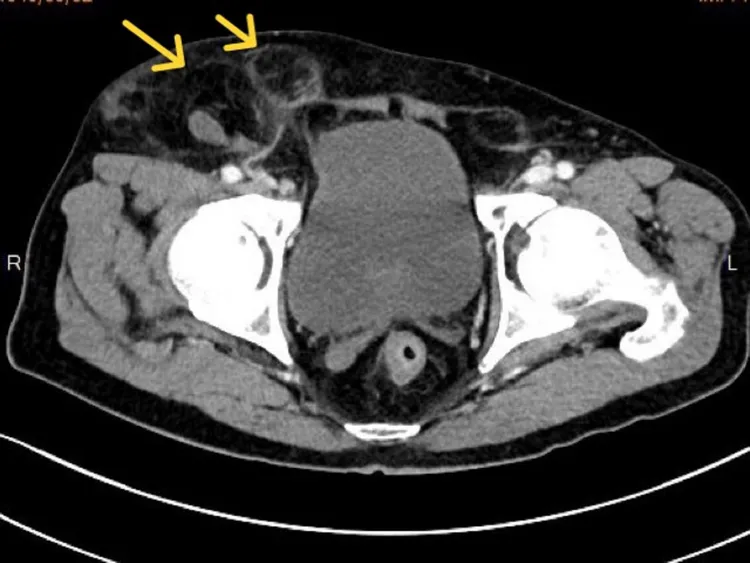

從電腦斷層影像可見兩個大小不一的疝氣囊(箭頭處)。高醫岡山醫院提供

蘇文隆說,手術過程中,確認病人同時發生股疝氣(femoral hernia)及間接型腹股溝疝氣(inguinal hernia),除將嵌頓的小腸及網膜復位,並使用立體剪裁人工網膜修補疝氣孔,以腹腔鏡縫合腹膜,及切除一小段已壞死的嵌頓小腸,手術歷時七小時終於順利完成。陳伯伯康復出院後回診,疝氣囊已完全消失,右側腹股溝回復平整,總算擺脫「頂著一大包走路」的困擾與不適。